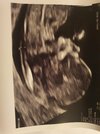

Ja już po badaniach prenatalnych na usg wszystko idealnie

wyniki krwi wysla mi do tygodnia na maila.

Dzidzia się wierciła a później włożyła kciuk do buzi i chyba zasnęła

Termin jednak na 8.07

czyli niecały tydzień wcześniej niż na pierwszym usg u gina.